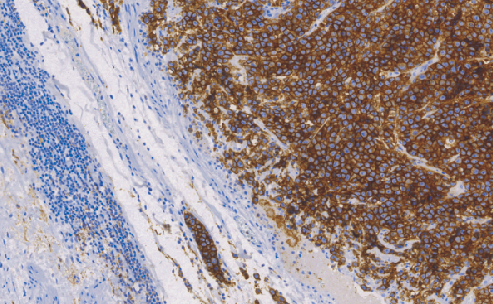

D2-40主要表达于淋巴管内皮细胞、胎儿睾丸组织和睾丸生殖细胞肿瘤中,而在微血管内皮中无表达。该抗体是正常和肿瘤组织中淋巴管内皮的一种新的标记物,可与内皮细胞标记联合应用于淋巴管内皮源性肿瘤的诊断

- 阳性部位:胞质

- 适用组织:石蜡切片

- 预处理:热修复